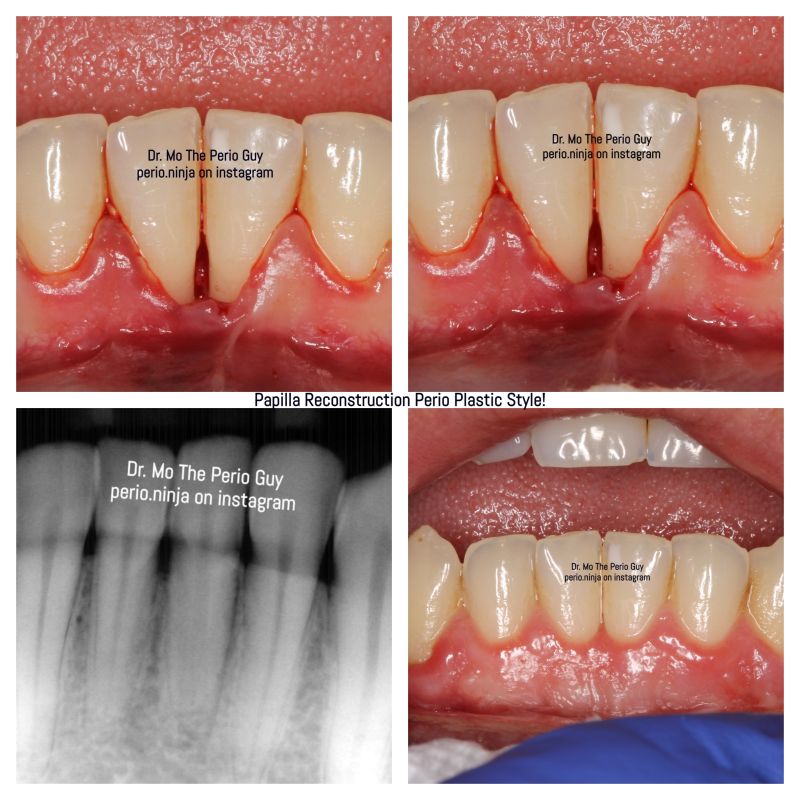

[著] Masana Suzuki [著] Fumiyo Yamaguchi [著] Masahito TakahashiA4判 / 164ページ2025-06-10 発売ISBN:978-4-7812-1131-2乳頭再建に特化した本邦初の書籍にして決定版!「難しい」「できない」と言われ続けてきた“歯間乳頭再建術”。本書では、「天然歯」「インプラント」「ポンティック」におけるそれぞれの乳頭の解剖学的特徴を示しながら、“乳頭再建”を成功に導くための考え方とテクニックを余すところなく解説。治療ステップの詳細を多数の大きな写真、リアルでわかりやすいイラストとともにビジュアルに解説しており、乳頭再建に特化した本邦初の書籍にして決定版といえる。歯周治療 インプラントクインテッセンス